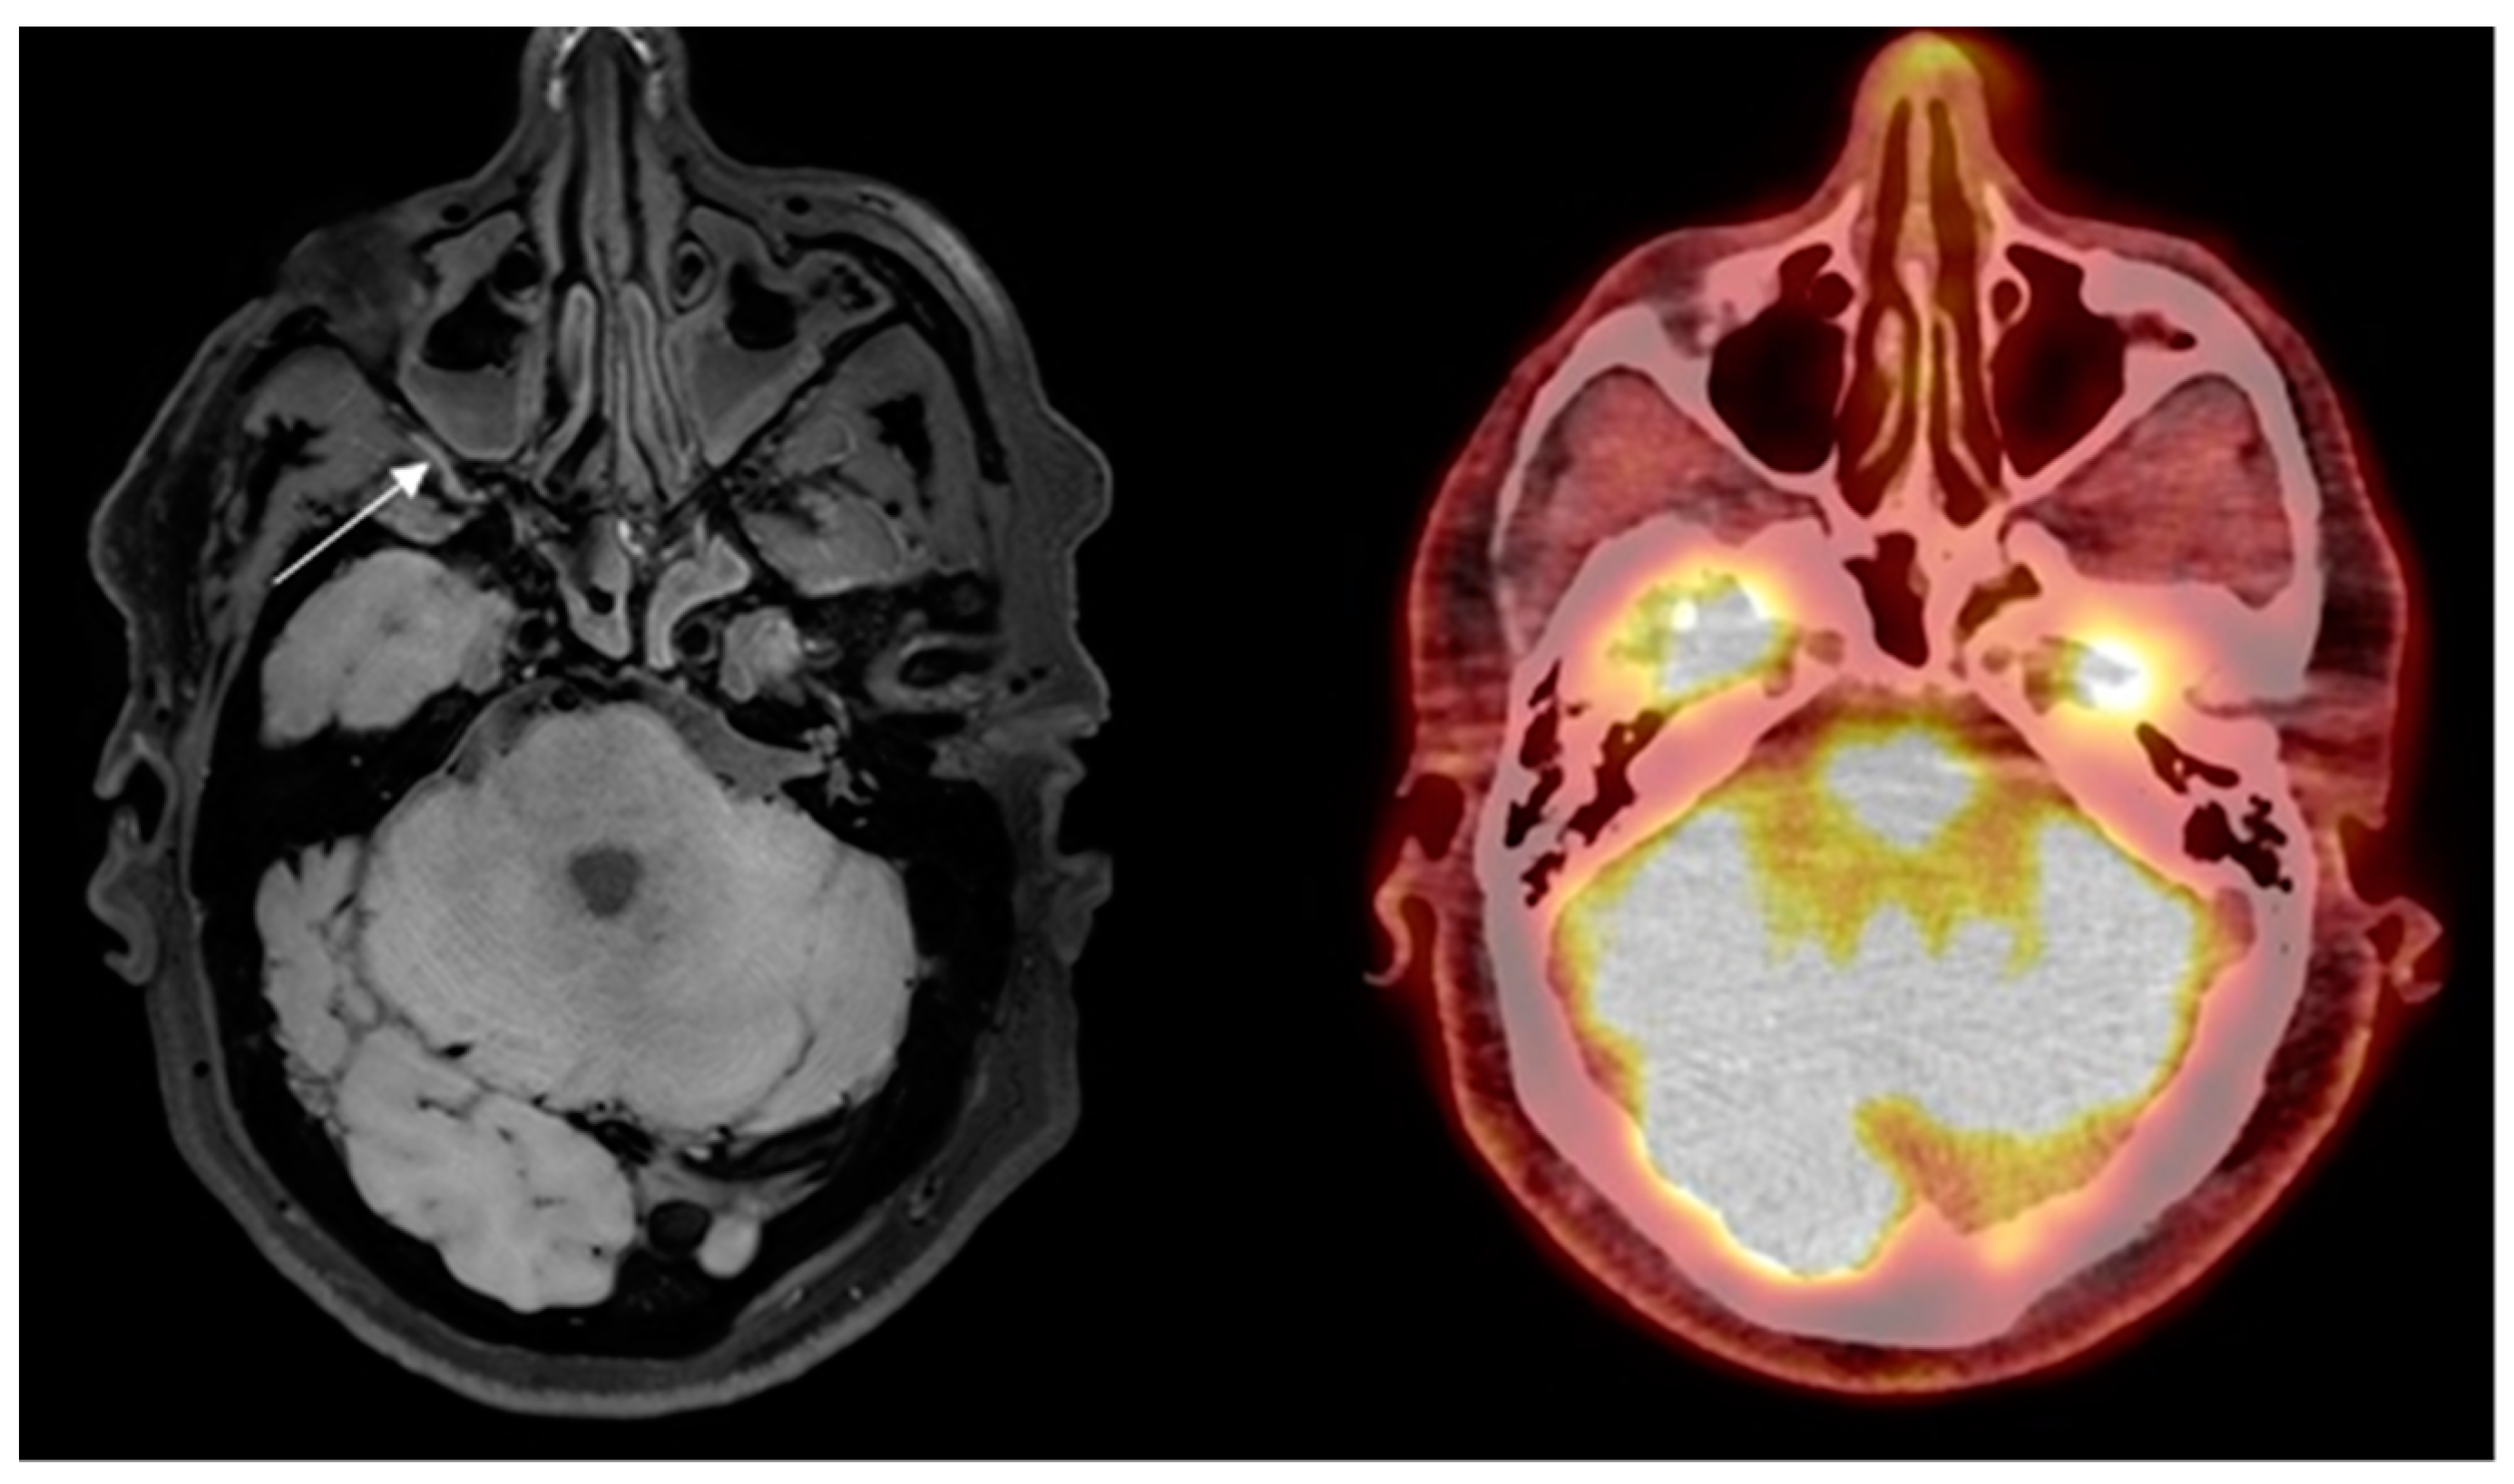

Eight out of ten patients were diagnosed with GCA. Of these eight patients, all eight were correctly identified as positive, independently, by both neuroradiologists reading the BB-MRI images. It was not possible to discriminate whether the inflammation was localized in the periadventitial tissue or in the adventitia. These patients were also correctly diagnosed from 2-[18F]FDG PET/CT and US examinations. Regarding the TAB results of the eight GCA-positive patients, one was a false negative, one renounced having the TAB performed, and the remaining six were positive. The patient whose TAB was deemed false negative had the final diagnosis of GCA based on clinical examination after six months, with results including fulfillment of three out of five ACR 1990 GCA classification criteria, elevated CRP, positive US, and positive 2-[18F]FDG PET/CT. No ophthalmological consequences of GCA were revealed in the patient by the neuroophthalmological examination. Two out of ten patients were diagnosed as GCA-negative, and were correctly identified as GCA negative by both neuroradiologists reading the BB-MRI images. Both patients were confirmed to be GCA negative by 2-[18F]FDG PET/CT, US, and TAB. There were no false negative or false positive 2-[18F]FDG PET/CT or US scans when using the final diagnosis after six months as the reference test. Four out of five participants in the control group were negative on the BB MRI, with one false positive. The 2-[18F]FDG PET/CT was GCA-negative, as per inclusion criterion. Compared with 2-[18F]FDG PET/CT as the reference test, BB MRI had a sensitivity, specificity, PPV, and NPV of 100.0% (95% CI: 63.1–100.0%), 85.7% (95% CI: 42.1–99.6%), 88.9% (95% CI: 68.4–100.0%), and 100.0% (95% CI: 100.0–100.0%), respectively, for diagnosing GCA. Due to motion artefacts, two BB MRI scans were of a poorer quality. This did not affect the diagnostic accuracy of BB MRI compared to the other imaging modalities or TAB. Hence, all 15 BB MRI scans were diagnostic. A head-to-head comparison of affected arteries on US, 2-[18F]FDG PET/CT and BB MRI showed some discrepancy. Generally, more arteries were evaluated as inflamed on US and 2-[18F]FDG PET/CT than on BB MRI (data not shown). In 14 of the 15 BB MRI scans, the two neuroradiologists made the same diagnosis. In the last case, a consensus diagnosis was made, favoring GCA, which was correct. Examples of imaging results of 2-[18F]FDG PET/CT and BB MRI are shown in Figure 1 and Figure 2.

Control subject misinterpreted with GCA in the right maxillary artery on high-resolution T1-weighted 3D black blood without contrast enhancement Magnetic Resonance Imaging (arrow) and no signs of vasculitis on 2-deoxy-2-[18F]fluoro-D-glucose positron emission tomography/low- dose computed tomography.

Figure 2 False-positive finding of GCA on BB MRI.

The potential benefits of BB MRI without contrast in visualizing vessel inflammation in GCA are high-resolution images, full coverage of cranial arteries, availability, short scan time (8 min), no radiation, and no administration of a contrast agent. Compared to US, the vertebral arteries are easily identified and well visualized. Furthermore, it can be performed in conjuncture with PET, using PET/MRI, with the potential of increasing the diagnostic yield by using two different imaging modalities. Additionally, the patient would benefit from having fewer appointments at the hospital. Limitations in this study are inhomogeneity in age between the control subjects and patients and the small sample size. For this reason, the reported sensitivity and specificity for BB MRI in diagnosing GCA are only indicative, and this explains the large confidence intervals. Preferably, all the BB MRI should have been performed before the TAB. As more arteries were inflamed, the unilateral TAB did not hinder the correct diagnosis from being made in GCA-positive patients. This also holds true for 2-[18F]FDG PET/CT. Furthermore, morphological changes after biopsy, i.e., subcutaneous air, can be visualized on low-dose CT, and the increased FDG-uptake due to inflammation after the biopsy can therefore be distinguished from vasculitis. The two (correct) GCA-negative patients on the BB MRI had their scan performed before the TAB. Further studies on possible changes on the BB MRI after biopsy are required. Subjects in the control group were not examined with US, to ensure that they did not have any vascular disorder, although no increased FDG-uptake indicating arteriosclerosis was visualized on 2-[18F]FDG PET/CT. In only one case did the findings from 2-[18F]FDG PET/CT and BB MRI differ. On the BB MRI, a hyperintense signal was observed in/related to the right maxillary artery wall, suggestive of GCA. This signal artifact can be due to slow flowing of the blood, as the suppression of the signal is flow-dependent [8,32]. We do acknowledge that there are other potential pitfalls producing a hyperintense signal in/related to the vessel wall, i.e., a thrombus with recanalization in the temporal artery which requires a TAB to exclude the GCA diagnosis. Care should therefore be taken not to misinterpret hyperintense signals due to incomplete blood signal suppression as inflammation in GCA.